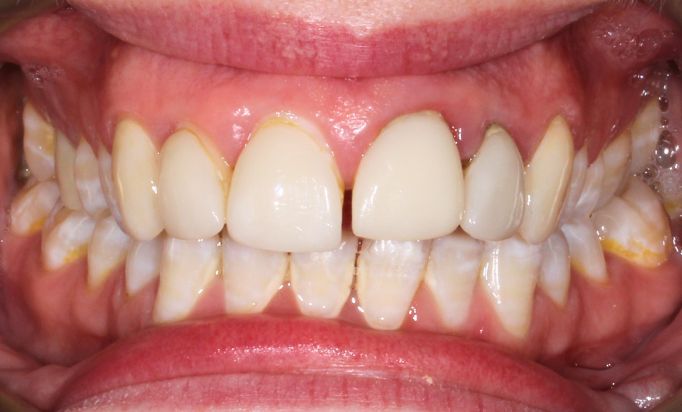

Periodontics

A secure, natural smile

Enjoy a radiant smile that reflects your personality.